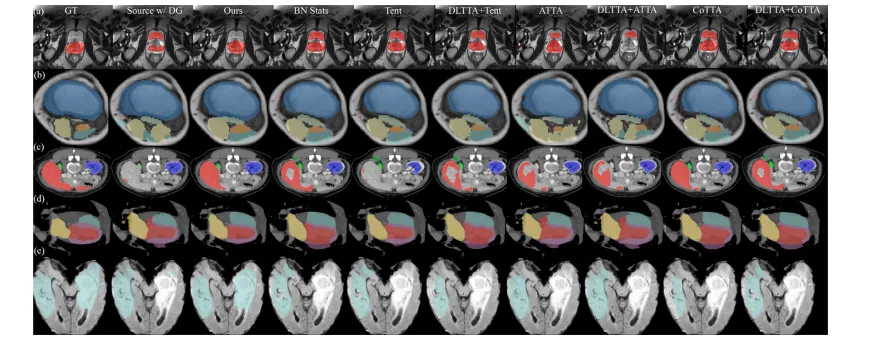

Fig. 3. Qualitative evaluation of benchmarked methods on the task of (a) cross-site MRI T2 prostate segmentation, (b) MRI mDixon → T1 muscle segmentation, © MRI T2 → CTabdominal segmentation, (d) MRI b-SSFP → CT heart substructure segmentation, and (e) MRI T2 → FLAIR brain tumor segmentation. Best viewed when zoomed in

图3. 基准方法在以下任务中的定性评估: (a) 跨站点MRI T2前列腺分割, (b) MRI mDixon → T1肌肉分割, © MRI T2 → CT腹部分割, (d) MRI b-SSFP → CT心脏子结构分割, (e) MRI T2 → FLAIR脑肿瘤分割。